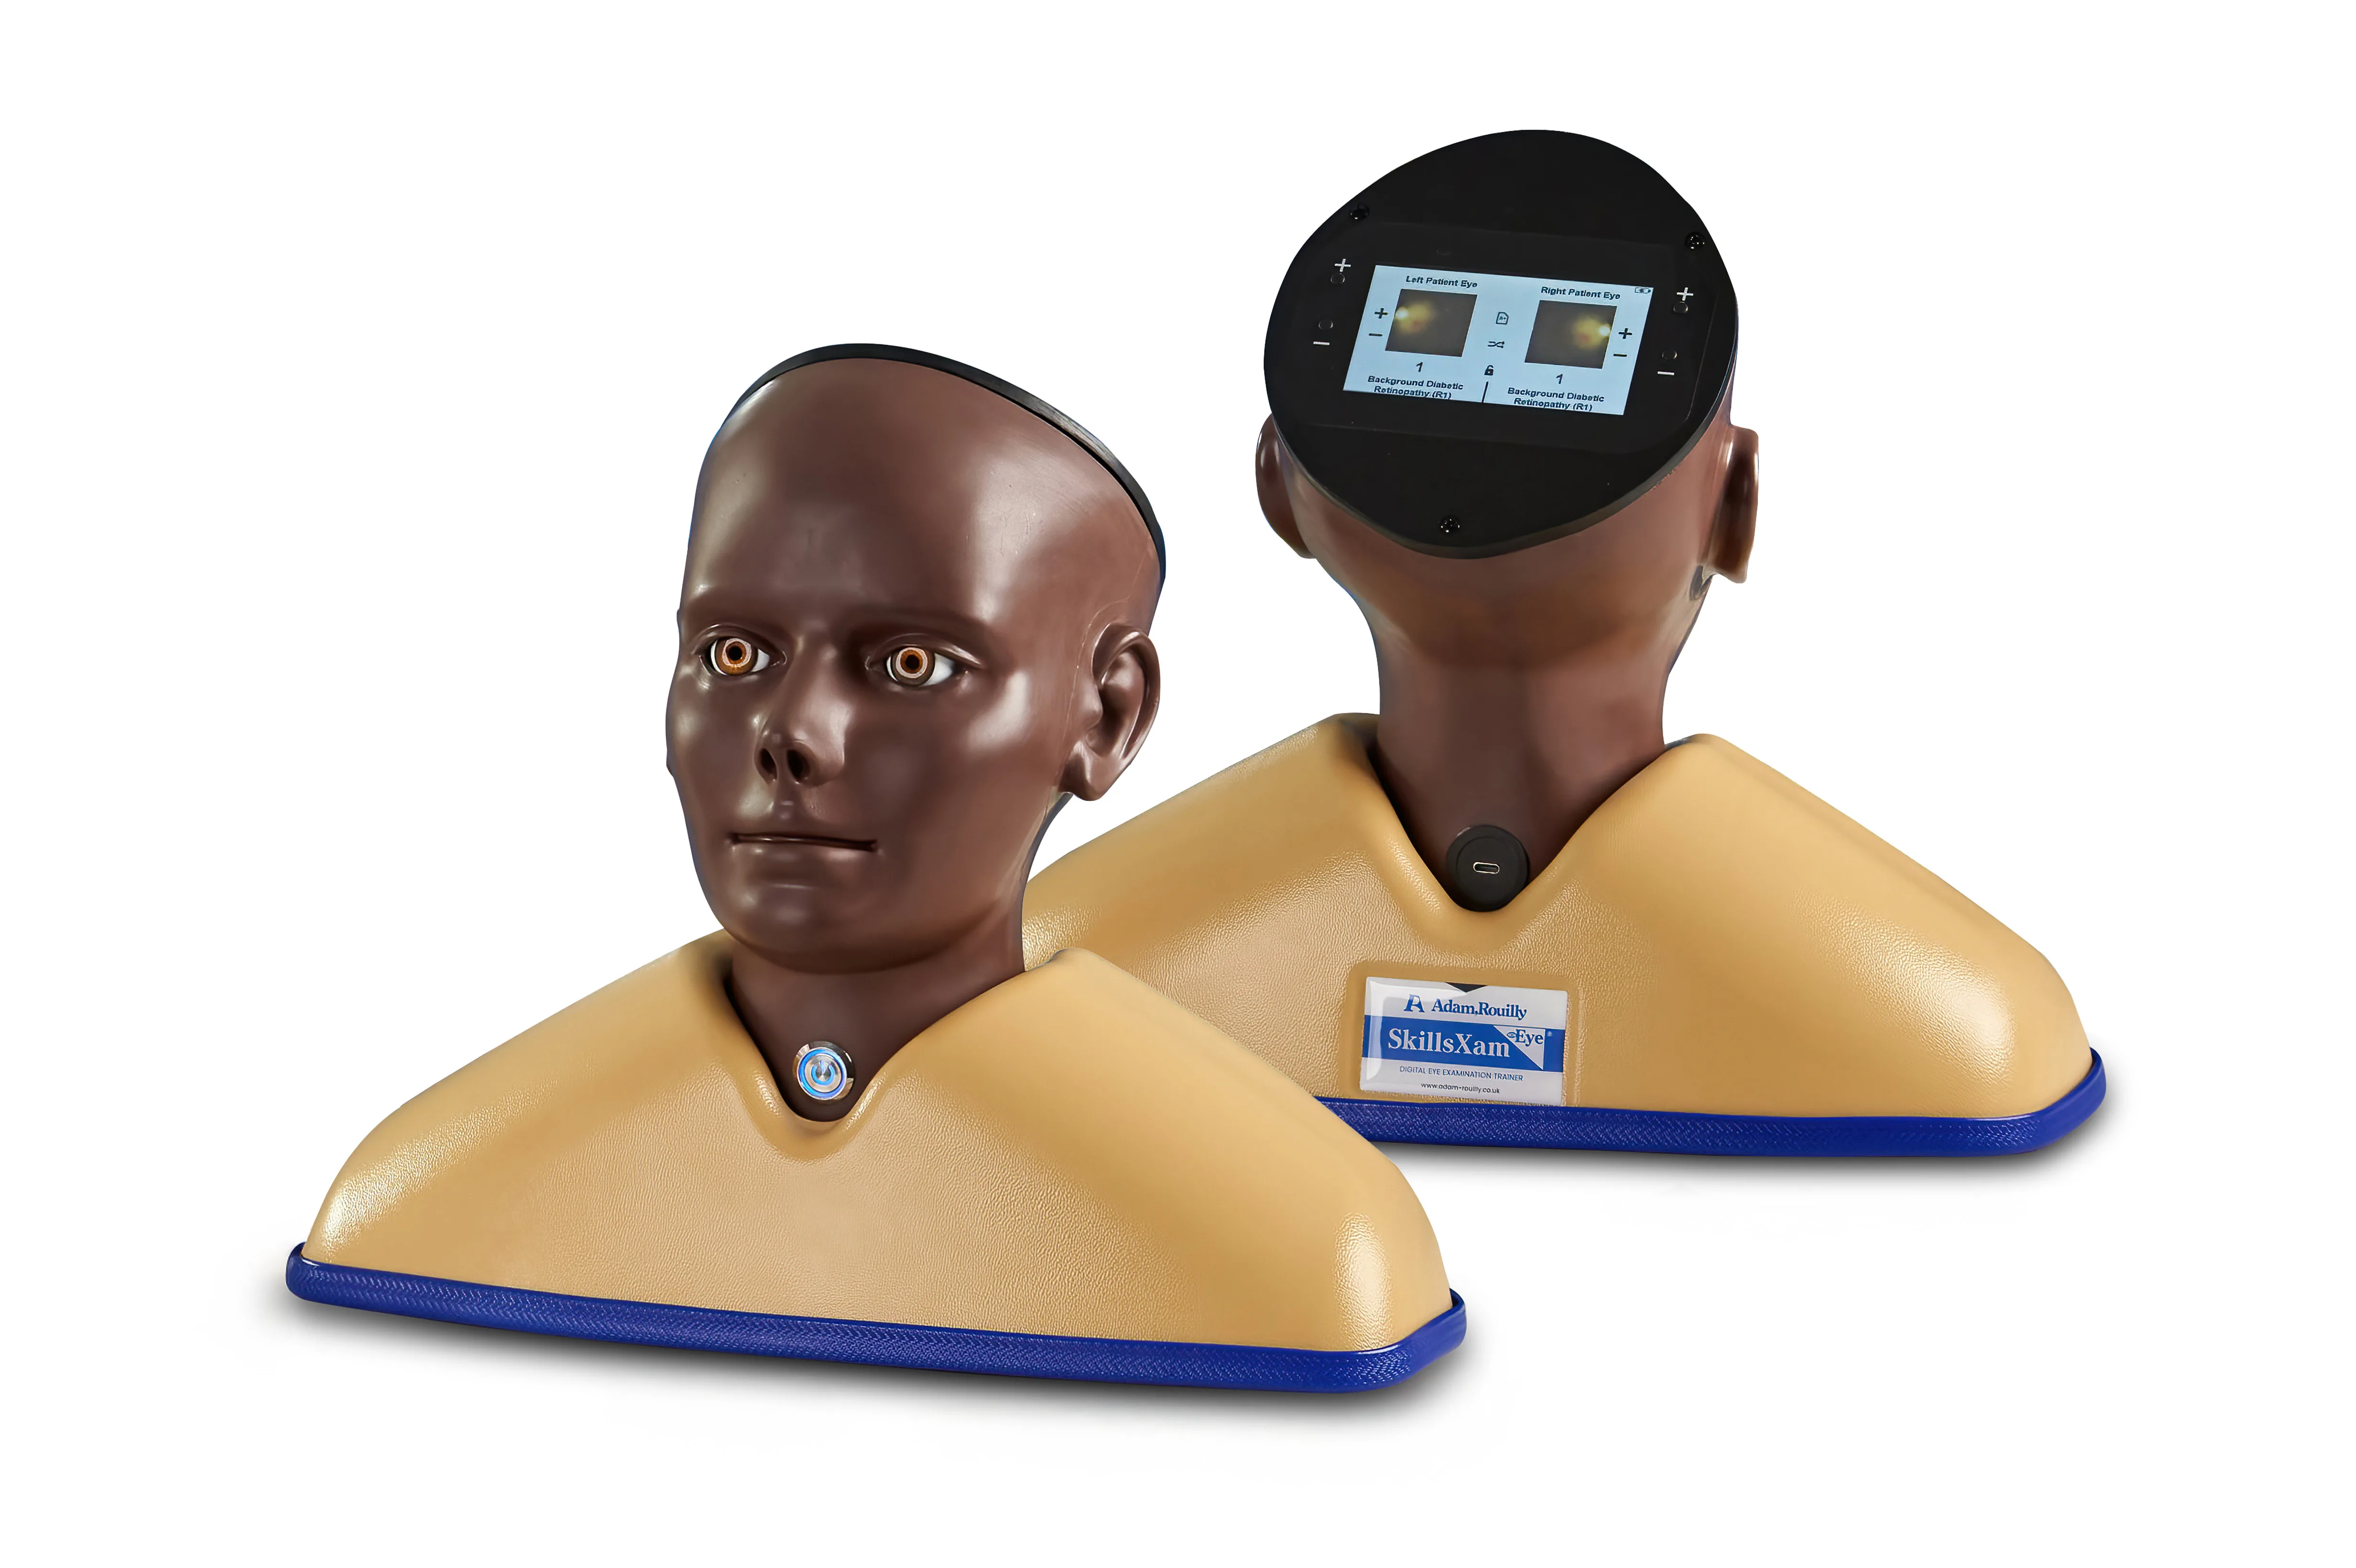

Enhanced Digital Eye Examination/Retinopathy Trainer, Dark

Developed in collaboration with Professor Vinod Patel, Professor, Diabetes and Clinical Skills, the Enhanced Digital Eye Examination Trainer takes ophthalmoscopy training to a new level of realism and inclusivity.

For the first time, advanced digital technology allows trainees to experience how the same eye condition can present differently in patients with light and dark skin tones. In darker-skinned patients, deeper pigmentation in the fundus reduces vessel visibility, a nuance replicated only in the AR503/50 Dark model. This provides learners with invaluable exposure to the clinical variations they will encounter in real practice, enhancing both competence and confidence. Offering two product versions enables trainees to gain an awareness of these visible variances.

Inside the model, conditions are displayed with greater clarity and true-to-life colour on high-resolution circular LCD screens. A 4.3-inch external touchscreen interface makes operation intuitive and effective, allowing users to preview, search, and select conditions or build customisable sets for teaching, self-directed learning, or examination scenarios.

The Enhanced Digital Eye Examination Trainer delivers an authentic, adaptive, and inclusive learning experience, redefining the standard in ophthalmoscopy training.